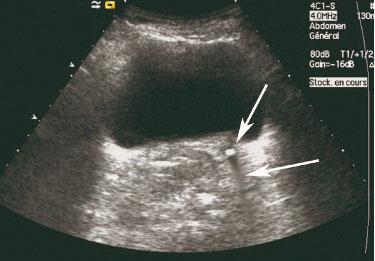

Échographie vésico-rénale. Hyperéchogénicité rétro-vésicale compatible avec une lithiase du bas uretère gauche avec cône d'ombre postérieur. Il s'agit de signes échographiques directs. Les calculs sont facilement visualisés au niveau rénal, de l'uretère proximal sous-pyélique et terminal juxta-vésicale à condition que la vessie soit remplie.